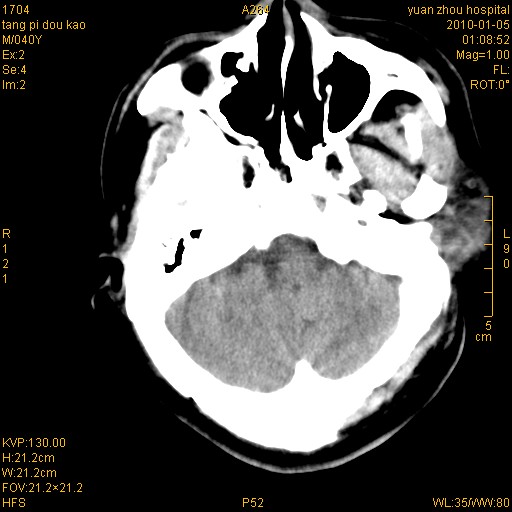

标题: CT23986:M 40Y 外伤数小时 [打印本页]

标题: CT23986:M 40Y 外伤数小时

1)左侧颞枕部硬膜外血肿。2)右侧额部硬膜下血肿。3)双侧额叶及右侧基底节下部脑挫裂伤。4)蛛网膜下腔出血。5)脑水肿。6)左侧前组筛窦及左侧额窦炎症。

挫裂伤,颅内血肿,蛛网膜下腔出血,脑肿胀。

弥漫性脑轴索损伤